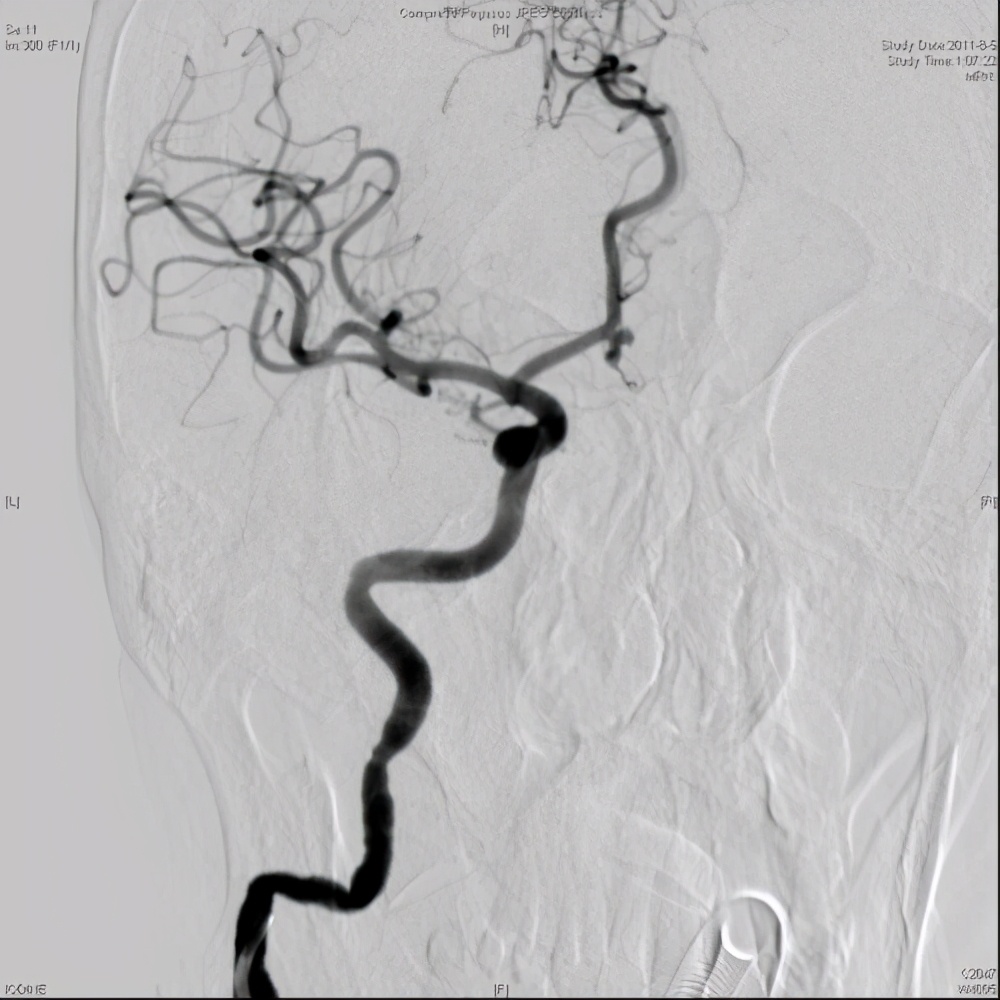

2、椎动脉造影

在早期的颈静脉球瘤动脉图像中,异常的肿瘤染色和供血动脉可见。在瘤体较大时,可了解患侧颈静脉受阻及压迫情况。椎动脉造影下颈静脉口区前肿瘤较多,术后及小脑动脉下方可向后移位,但亦可见浅表部位的肿瘤染色,如血管及某些缺乏上皮样肿瘤或蛛网膜囊肿,可与肿瘤染色、深部脑膜瘤及颈静脉瘤相鉴别。